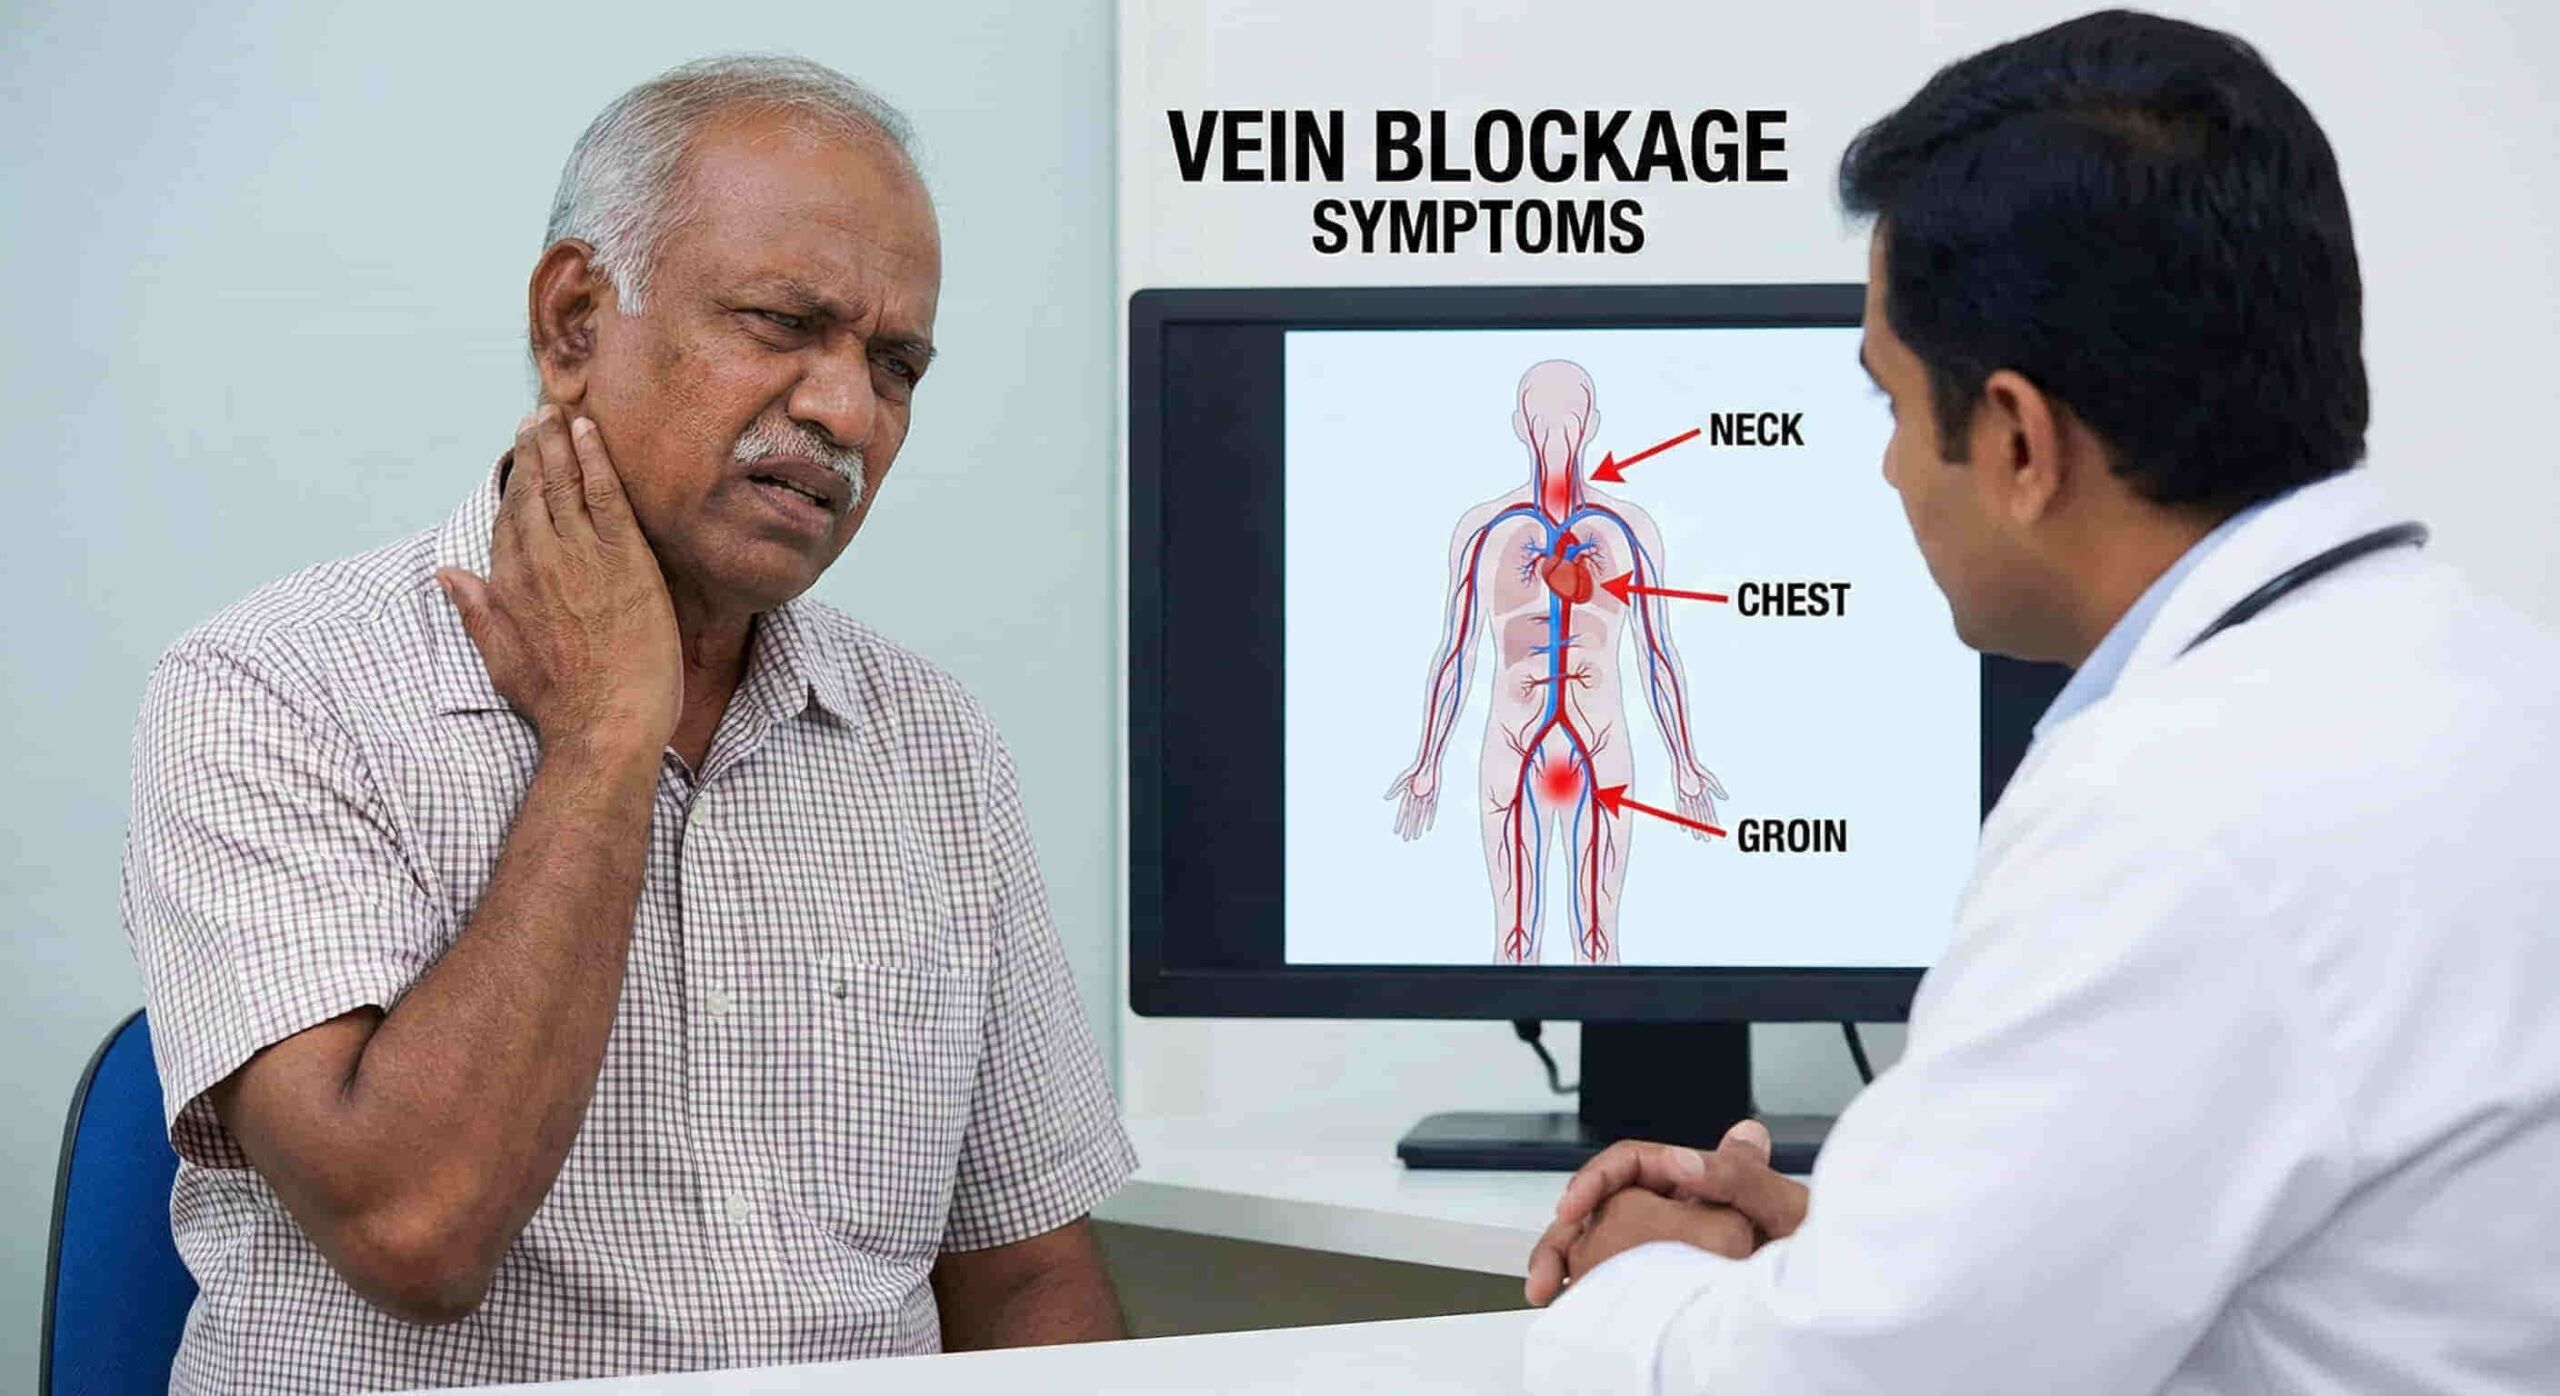

- For patients who depend on long-term dialysis or intravenous therapy, reliable central venous access isn’t optional—it’s life-sustaining. But repeated catheter use can close off the usual veins in the neck and chest, leaving patients with limited options.

- Exhausted Access: Patients who have no usable veins left in the upper body (neck, chest, or arms) due to multiple previous blockages.

- Failed Recanalization: When attempts to reopen blocked neck veins have not been successful.

Because the IVC is near the spine and major arteries, there is a small risk of bleeding (hematoma). However, because Dr. Ram uses high-definition imaging guidance, these risks are minimized.